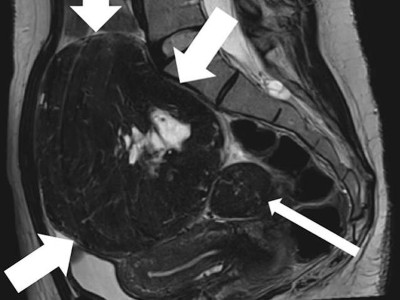

Ein Abstrich vom Gebärmutterhals wird auf ein Objektivträger geschmiert/© Tatiana Buzmakova / Getty Images / iStock (Symbolbild mit Fotomodellen), MRT des Beckens: Uterus und Ovarialtumoren/© Hosten AK et al. / all rights reserved Springer Medizin Verlag GmbH, Ultraschall eines Adnextumors/© Markus Hoopmann, Mehrere Personen erhalten Chemotherapie/© FatCamera / Getty Images / iStock (Symbolbild mit Fotomodellen), Subtypen des epithelialen Ovarialkarzinoms/© Springer Medizin, Frau mit Kopftuch und Infusion/© FatCamera / Getty Images / iStock (Symbolbild mit Fotomodell), Gewinner des Galenus-von-Pergamon-Preises 2025 in der Kategorie Specialist Care/© Marc-Steffen Unger, Frau bereitet einen Smoothie zu/© Tijana Simic / Getty Images / iStock (Symbolbild mit Fotomodell), Subkutane Injektion/© myskin / stock.adobe.com (Symbolbild mit Fotomodel), Eine ältere Frau bekommt eine intravenöse Therapie/© peopleimages.com / stock.adobe.com, Ärztin betrachtet Mammografie-Befund/© Gorodenkoff / stock.adobe.com (Symbolbild mit Fotomodellen), Frau bei Mammografie-Untersuchung/© Myroslava / Stock.adobe.com (Symbolbild mit Fotomodellen), Frau setzt sich ein Pflaster auf den Schenkel/© svetikd / Getty Images / iStock (Symbolbild mit Fotomodell), Lungenmetastasendiagnostik/© Krämer S. et al. / all rights reserved Springer Medizin Verlag GmbH, Verlagerung von Oberbauchorganen in den Thorax/© Koop H (Mit freundl. Genehmigung der Radiologischen Abteilung), Multiple Papeln auf der Hand bei chronischer Prurigo/© E. Steffens et al. doi.org/10.1007/s00105-023-05131-8 unter CC-BY 4.0, Hysterektomie/© nkeskin / Getty Images / iStock, Search Icon, Person setzt DNS-Probe in Maschine ein/© Vit Kovalcik / stock.adobe.com, Mann raucht Joint/© Daniel Sierralta / Westend61 / stock.adobe.com (Symbolbild mit Fotomodell), Blut in Toilette/© stylefoto24 / stock.adobe.com